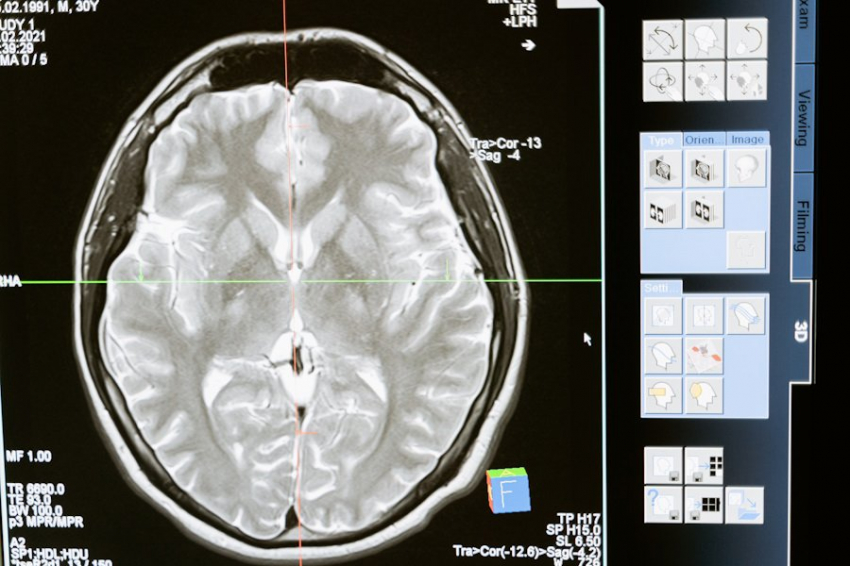

Память человека — это один из самых сложных и загадочных процессов, происходящих в мозге. Специалисты утверждают, что память не функционирует как жёсткий диск компьютера, где информация хранится в отдельных ячейках. Вместо этого воспоминания распределены по различным областям мозга и зашифрованы в сложных нейронных связях. Такой подход к хранению информации делает возможным воспроизводство событий даже в случае утраты части нейронов. Это означает, что информация не исчезает полностью, а сохраняется в виде уникальных комбинаций между клетками.

Интересно, что такая организация памяти позволяет теоретически запоминать бесконечное количество событий. Один и тот же нейрон может участвовать в формировании самых разных сочетаний, создавая множество уникальных конфигураций, каждая из которых соответствует определённому воспоминанию. Это объясняет, почему люди могут помнить о событиях, происходивших в разные моменты жизни, и как они могут связывать разные воспоминания друг с другом.